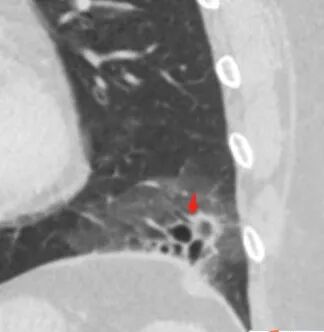

胸CT:左肺下叶囊腔,壁厚薄不均,可见壁结节,囊腔内可见断裂小梁,部分融合,周围边界较清楚GGO,胸膜牵拉,可见血管集束、支气管充气征,冠状位部分层面可见支气管在囊腔边缘截断。考虑:囊腔型腺Ca。鉴别:肺大疱感染,CPAM等。

囊腔有张力,外形有分叶,壁厚薄不均,有间隔,有强化

1、左肺下叶外基底段不规则囊腔样病灶,囊腔内有条形影及血管穿行。

2、囊壁薄厚不均匀,稍显僵硬,有壁结节(对应边缘分叶等)、结节强化明显。

以上两条几乎将肺囊肿彻底排除在外,且高度怀疑新生物!

3、灶周环以大范围磨玻璃影,非常均匀,没有重力分布趋势,分叶状,边界隐约可变。

4、冠状位部分层面可见支气管在囊腔边缘截断。